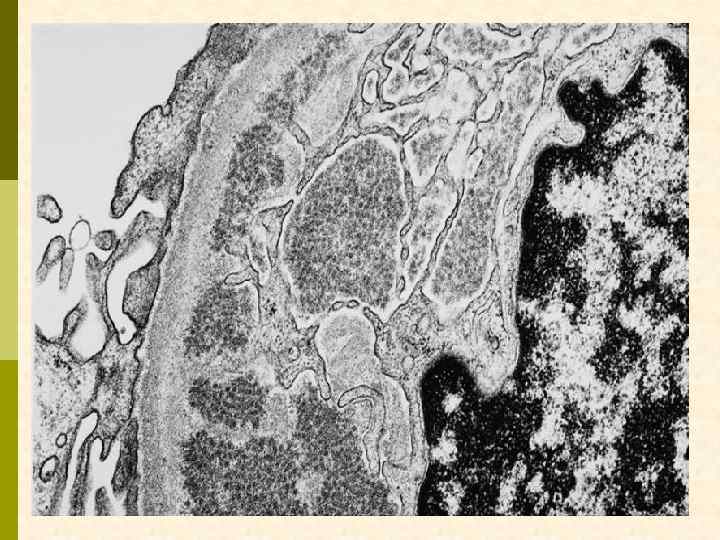

ИММУНОТАКТОИДНАЯ ГЛОМЕРУЛОПАТИЯ ГБМ н. ГБМ

ИММУНОТАКТОИДНАЯ ГЛОМЕРУЛОПАТИЯ